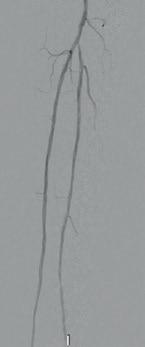

Arteriogram, left lower extremity

An arteriogram of the left lower extremity was performed via antegrade left common femoral artery access based on preoperative review of the lower extremity arteriogram from Uzbekistan. Scattered non-calcified plaque with moderate to high-grade stenoses were identified in the proximal and mid superficial femoral artery. Diffuse severe calcified tibial artery disease was identified. There was a long segment stenosis of the proximal and mid posterior tibial artery coupled with a more distal occlusion. The proximal peroneal artery was calcified and occluded with distal reconstitution identified. There was complete occlusion of the anterior tibial artery (Figure 2).